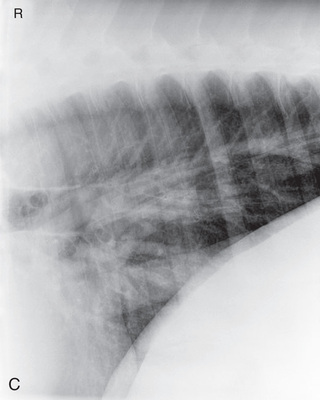

| Thorax | Lateral (Fig. 24.60) | Affected side | Horizontal beam on opposite side. | See comments later for specifics: | Patient standing. Portable unit not powerful enough. |

| Abdomen | Lateral (Fig. 24.61) | On side (most lesions on midline). | Opposite side. | Last rib for small horses: | Multiple laterals required for larger patients. |